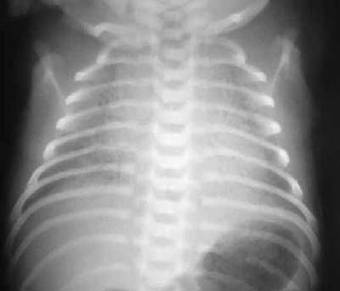

Figura 87-1

. Opacidade pulmonar bilateral, simétrica, difusa. Observe os broncogramas aéreos.